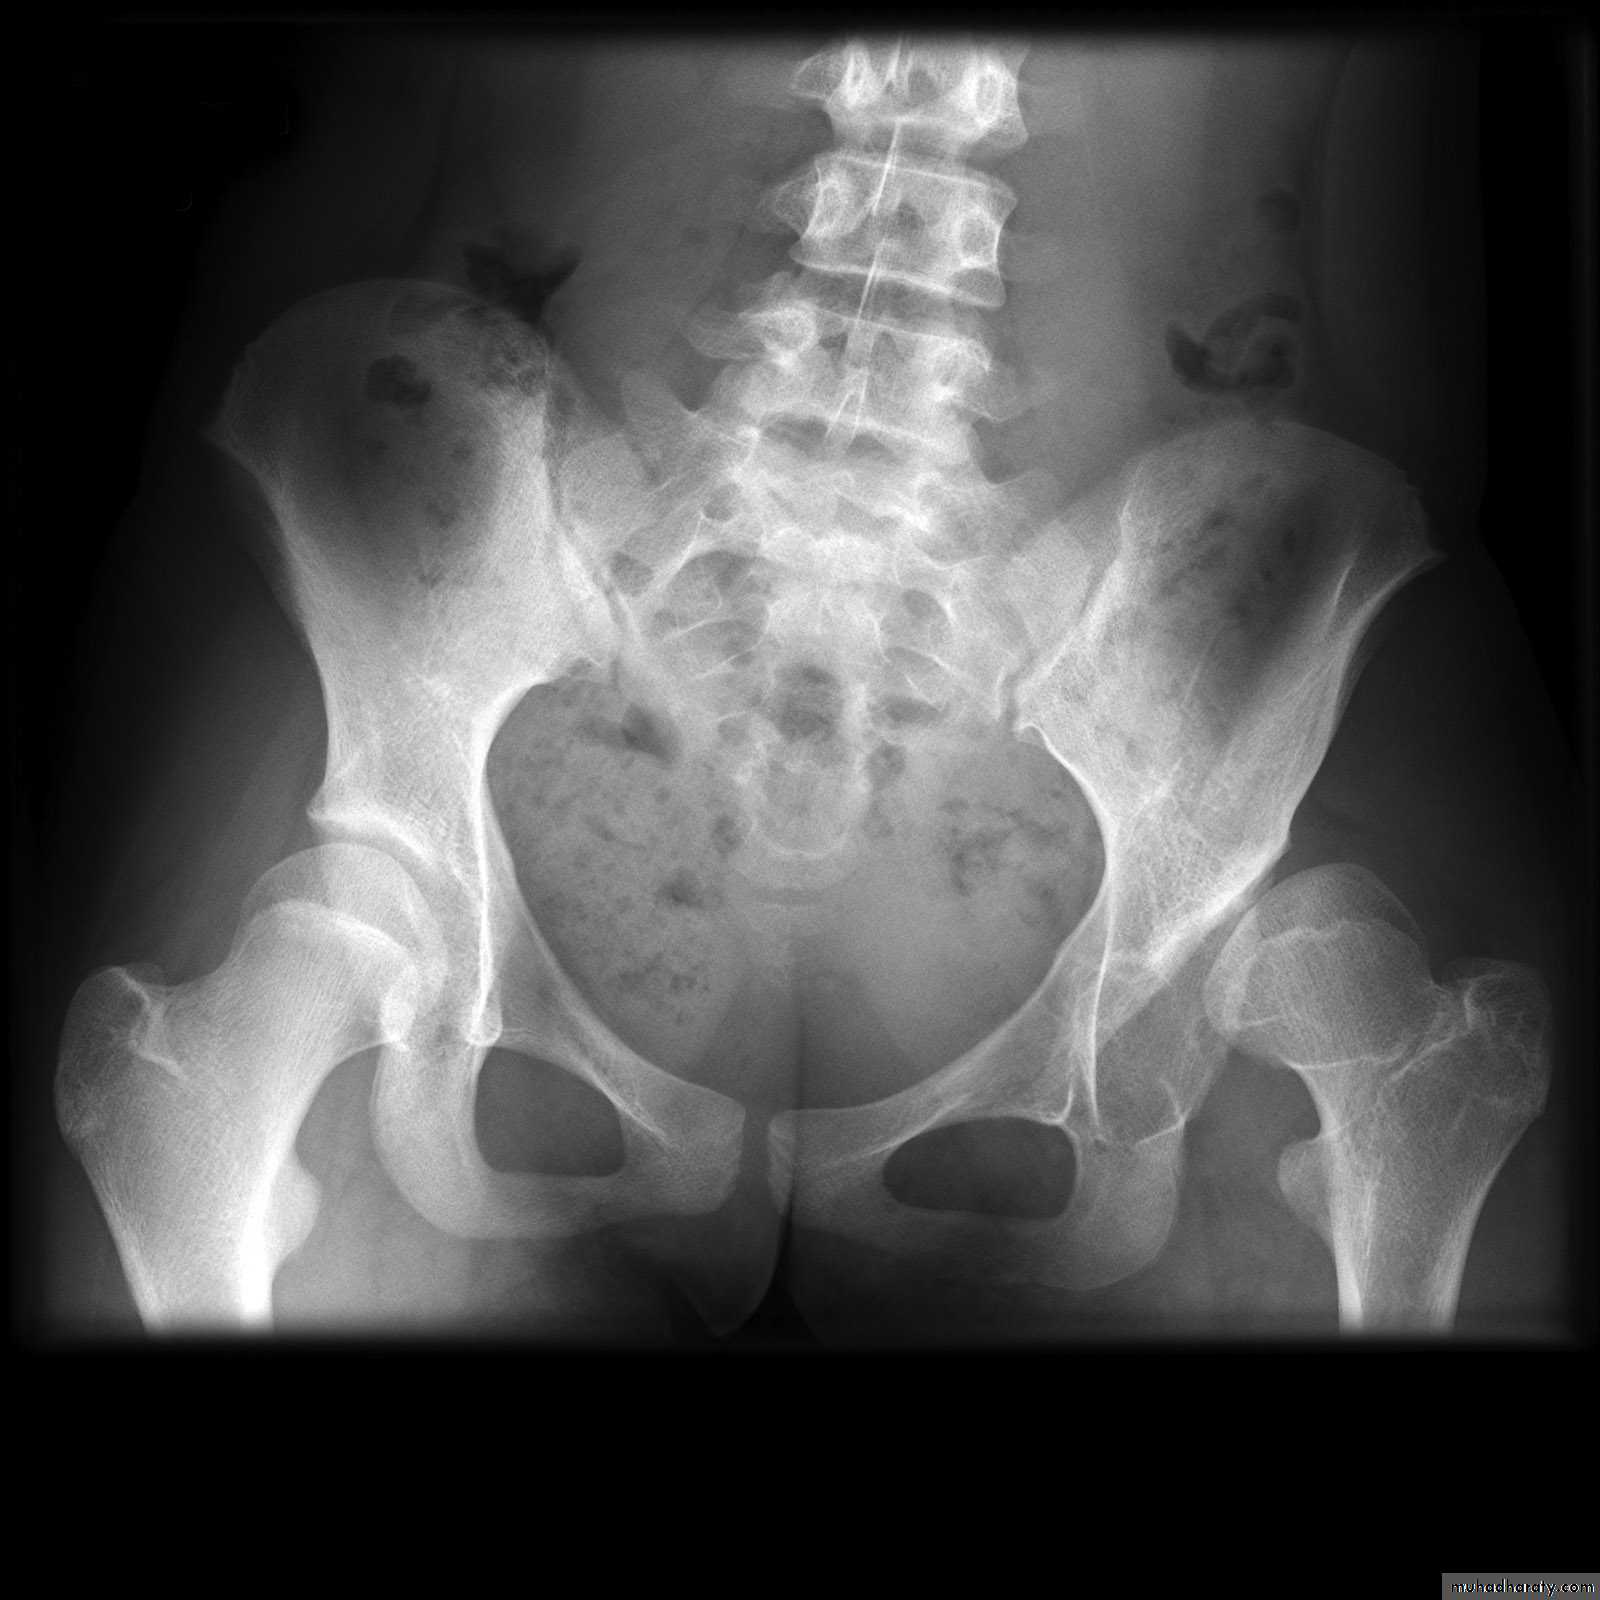

DEVELOPMENTAL DYSFLASIA OF HIP (CONGENITAL DISLOCATION OF THE HIP)

• An abnormally lax joint capsule allows the femoral head to fall out of the acetabulum, leading to deformation.• Predisposing factors for the development of CDH are:

• * Abnormal ligamentous laxity (effect of estrogen; fema1e:male = 6:l)

• * Acetabular dysplasia .

• CDH occurs most commonly (70%) in the left hip. Bilateral involvement is seen in 5%.

• Radiographic features

• US (commonly used today) at 1-3 months

• * Normal femoral head is covered at least 50% by acetabulum , In CDH < 50% of femoral head is covered by acetabulum .

Plain film

At 3-6 months :By doing special veiw (Von Rosen veiw )by abduction of the thigh 45 degree and internal rotation .

In DDH the lines that drown through the femura will meet in higher level than the normally should at lumbosacral joint .

6 months and later

* AP veiw ( femural epiphysis are visualized ):* Superolateral displacement of proximal femur (disturbed shenton’s line )

* Increase in acetabular angle

* Small capital femoral epiphysis

Femoral head is located lateral to Perkin's line

* Other features that are sometimes present

Abnormal sclerosis of the acetabulum

Shallow acetabulum

Formation of a false acetabulurn

Delayed ossification of femoral head